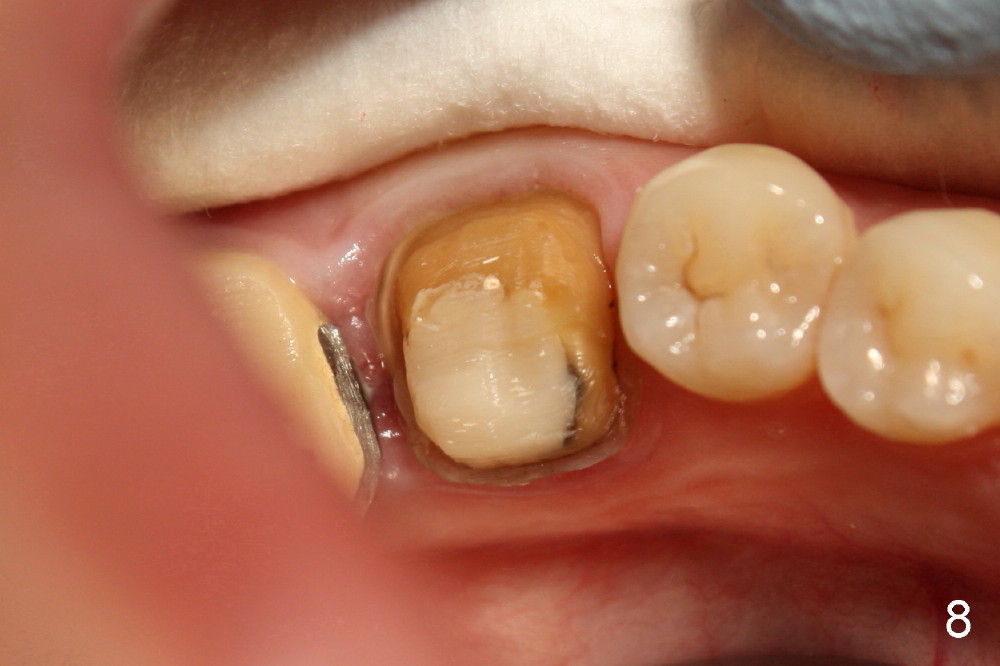

近中根管扩大麻烦,只能慢慢来,逐渐失去working length,X光片证实(图五:MB:30/.06主牙胶尖; ML:十号扩大针),之后继续努力,向根尖进军。近中舌侧根管主要使用hand files,直到三十号,尽量往侧壁拉,让断针松弛,最后利索通过rotary file 30/.06一次,充填前再拍摄一张根尖片,希望无意中断针被冲洗出来(病人期待能把断针取出,她胆小,好不容易下定决心重做根管治疗),结果白日做梦,断针还在原处(图六),偶尔能取出自己造成断针,这次却不行,反正丑媳妇不怕见公婆,在二点五倍loops下,断针始终看不见。最后完成根管充填(四个根管都用30/.06主牙胶尖)和buildup(图七),充填好像不尽人意,这时精疲力竭,好在病人还感激,接着制作临时牙冠,打发病号。术后一两天病人还有些疼痛,只好观察,后来把她忘却。今天术后两周她突然回诊所,昨天把临时牙冠咬断(图八),我们重做临时牙冠,用永久性粘固粉,她准备明年做两个牙冠,想充分使用牙科保险钱。最振奋人心的是她张口痛完全消失,看样子术前没有TMD,虚惊一场。